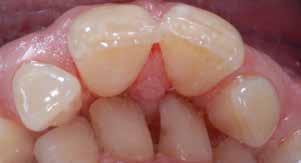

Nel corso del primo esame obiettivo vengono valutati forma, colore e confgurazione della lingua Figg. 14-15

La lingua può essere stretta, lunga o larga, senza che da tali riscontri si possano trarre conclusioni sulle dimensioni relative della lingua stessa. Le modifcazioni della posizione e della mobilità della lingua sono spesso associate ad aderenze del frenulo linguale Fig. 16 Le impronte dei contorni dentali presenti sul margine della lingua indicano una discrepanza tra la larghezza dell’arcata dentale e la larghezza della lingua stessa. In questi casi la terapia ortognatodontica non deve assolutamente ridurre ulteriormente il cavo orale (come, ad esempio avviene con le estrazioni dei premolari) ma piuttosto aumentare lo spazio a disposizione per favorirne il corretto funzionamento (Ferrante 1996). Una valutazione approssimativa delle dimensioni della lingua in rapporto alle dimensioni della cavità orale può essere effettuata basandosi sulla teleradiografa. La lingua rappresenta il motore della terapia elastodontica; infatti, essa è un volume tridimensionale che assume un ruolo morfogenetico in fase di crescita, un ruolo equilibratore in fase intermedia ed un ruolo compensatore in fase adulta (Stefanelli 2003).

Forme diverse della lingua: spanciata ed a punta.